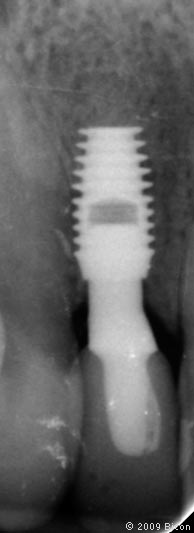

64. Рентгенограмма после установки

65. Рентгенограмма после установки